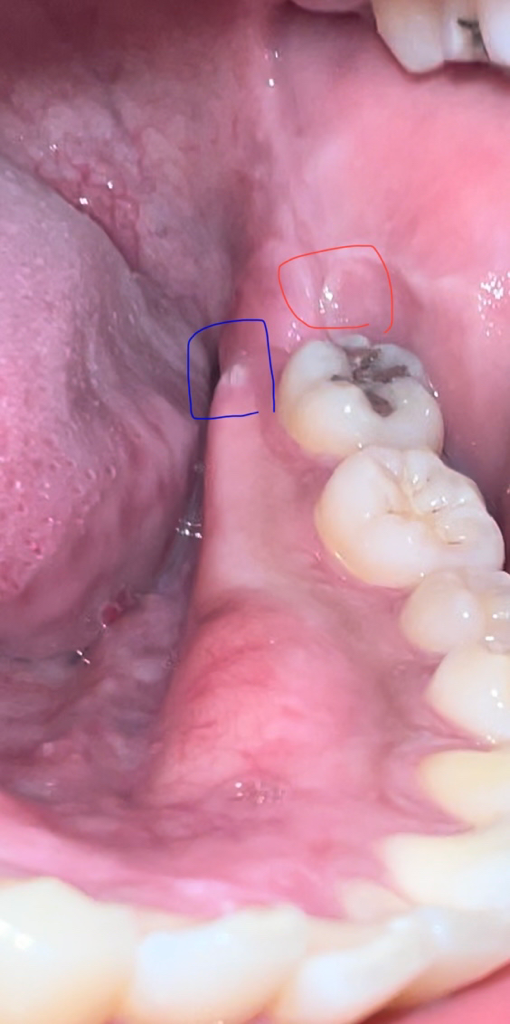

사랑니 발치 후 잇몸 뼈? 돌출

사랑니 발치 후 잇몸 옆 부근에 뭔가 생긴것 같습니다.

파란색 동그라미 부분이 무언가 튀어나온 부분인데요, 뾰족하고 날카로운 이빨? 같이 돌출되어 있습니다. 이게 대체 뭘까요?